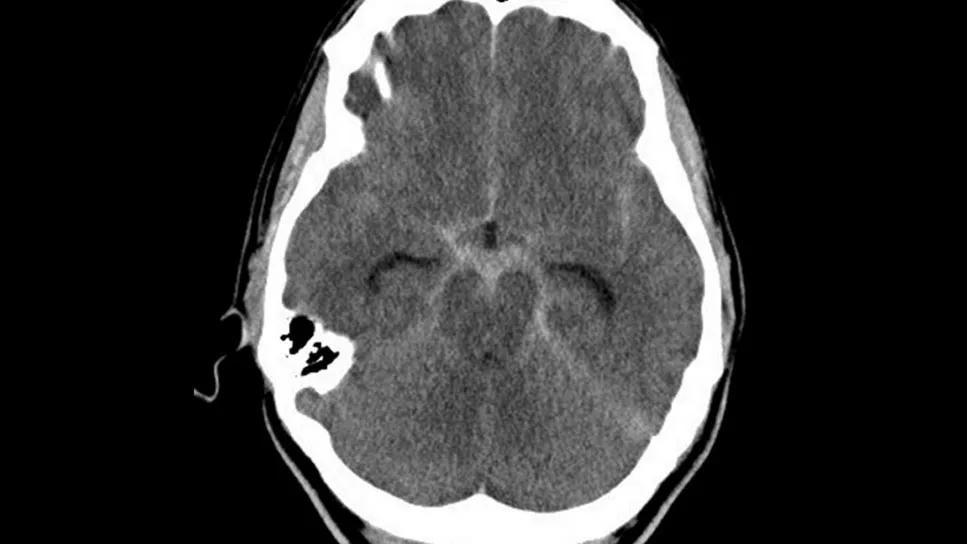

brain scan showing perimesencephalic subarachnoid hemorrhage

Evaluation with digital subtraction angiography (DSA) to assess “benign” perimesencephalic subarachnoid hemorrhage (PMSAH) is still warranted in addition to computed tomography angiography (CTA) in the search for an underlying ruptured aneurysm. After complete assessment, a patient with nonaneurysmal PMSAH without hydrocephalus can be managed with a shorter hospital stay and less strict monitoring, as clinical outcomes tend to be favorable.

PMSAH is commonly referred to as benign because a source of bleeding often cannot be identified and recovery is usually uncomplicated. But in rare cases, an initially undetected ruptured aneurysm is the culprit. Investigation usually begins with CTA, often followed by DSA — a more invasive test considered to be the gold standard for detecting an intracranial vascular lesion. As CTA technology has advanced, the need for DSA investigation has been called into question.